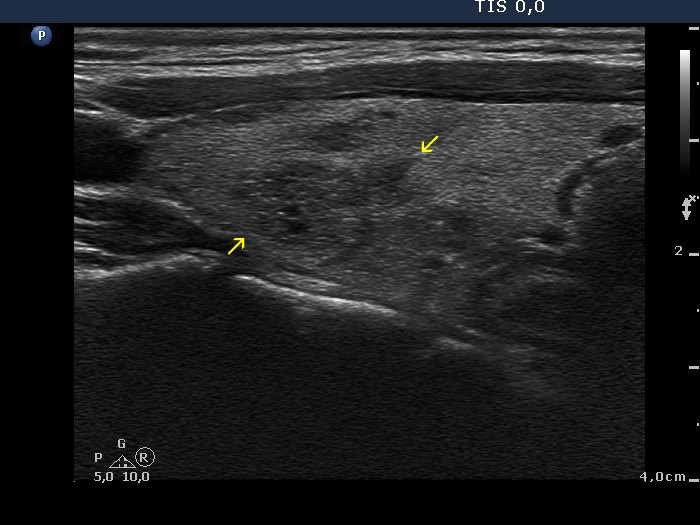

Oxyphilic variant of papillary carcinoma in an autonomously functioning nodule (histology) - case 2022

Transverse scans

Longitudinal scans

The nodule has irregular borders, there are some spiculations with sharp angles (yellow arrows) and some protrusions marked with red arrow.